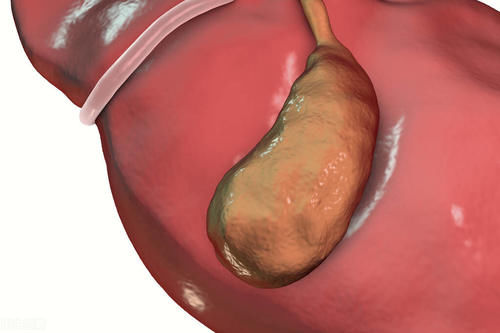

Jun 04, 21 · · 胆囊炎与胆结石的关系 1、关系密不可分,很少单独存在 胆结结石可引起胆囊炎(胆囊结石长期存在或胆囊结石嵌顿于胆囊颈部,引发继发性病变,如:胆囊炎);胆囊炎也可引起胆结石(发生胆囊炎后能促进胆囊结石的形成和增多)。胆囊炎是胆囊的炎症,通常是由结石阻塞胆囊管引起的。 典型的症状表现为腹痛、发热和恶心。 腹部超声检查可以观察到胆囊炎症。 通常可使用腹腔镜切除胆囊。 胆囊是一个体积较小的、梨形的囊性器官,它位于肝的下方。 它贮存胆汁,胆汁是由肝脏产生的可帮助消化的一种液体。 当需要胆汁时,通常是当人们进食时,胆囊收缩挤压胆汁使其经胆管流入小肠胆囊炎的症状一般会比较严重,那么为什么会得胆囊炎呢? 1、肥胖 经过研究发现,肥胖的人患上胆囊炎的几率会比正常人高,所以肥胖也是导致形成胆囊炎的重要危险因素。 2、饮食习惯 生活中过度使用胆固醇食物的人群患上胆囊炎的几率也会比较高,很

膽囊炎 是 細菌性感染 或 化學 性刺激 (膽汁 成分改變)引起的膽囊炎性病變,為 膽囊 的 常見病 。 在 腹部外科 中其 發病率 僅次於 闌尾炎 ,本病多見於35~55歲的中年人,女性發病較男性為多,尤多見於 肥胖 且多次 妊娠 的婦女。Jun 16, 21 · 胆囊炎的症状 1、如果上腹有剧烈的疼痛,很有可能是患胆囊炎的前期症状,所以当你发现自己有腹胀,剧烈疼痛的现象,一定要及时到医院检查 2、如果经常出现恶心,甚至会伴有呕吐,都是有可能进一步确认为胆囊炎的,所以有了此症状一定要及时就医 3、发热,身上冷膽囊炎 (Cholecystitis)是指發生於 膽囊 的 炎症 ,症狀包括右上 腹部疼痛 、噁心、嘔吐、偶有發燒 。 多半在急性膽囊炎之前會有 膽絞痛 的症狀 。